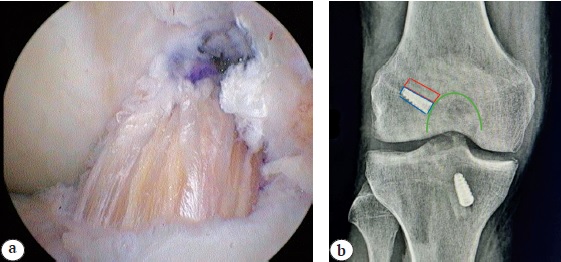

Предложенный нами способ пластики ПКС включает артроскопию коленного сустава, мобилизацию связки надколенника, продольное рассечение перитенона и получение трансплантата из средней трети связки надколенника с двумя прилежащими костными блоками, обработку трансплантата с целью получения необходимого размера, рассверливание каналов в латеральном мыщелке бедренной и медиальном мыщелке большеберцовой костей в местах анатомического прикрепления ПКС под артроскопическим контролем, проведение в каналы и фиксацию аутотрансплантата интерферентными титановыми винтами, ушивание перитенона. Расположение и фиксация проксимального костного блока в мыщелке бедра производится таким образом, чтобы основание костного блока и основание интерферентного винта находились в одной плоскости с медиальной стенкой латерального мыщелка бедренной кости (рис. 2). Рассверливание канала в наружном мыщелке бедренной кости выполнялось через переднемедиальный артроскопический порт при сгибании коленного сустава под углом 120°. Рассверливание канала в медиальном мыщелке большеберцовой кости проводилось при помощи стереотаксического направителя, установленного под углом 55°.

Рис. 2. Расположение трансплантата и интерферентного винта по отношению к наружному мыщелку бедра: а — артроскопическая картина; b — рентгенологическая картина

Fig. 2. The graft and interferential screw positioning with respect to lateral femoral condyle: a — arthroscopic view; b — x-ray view